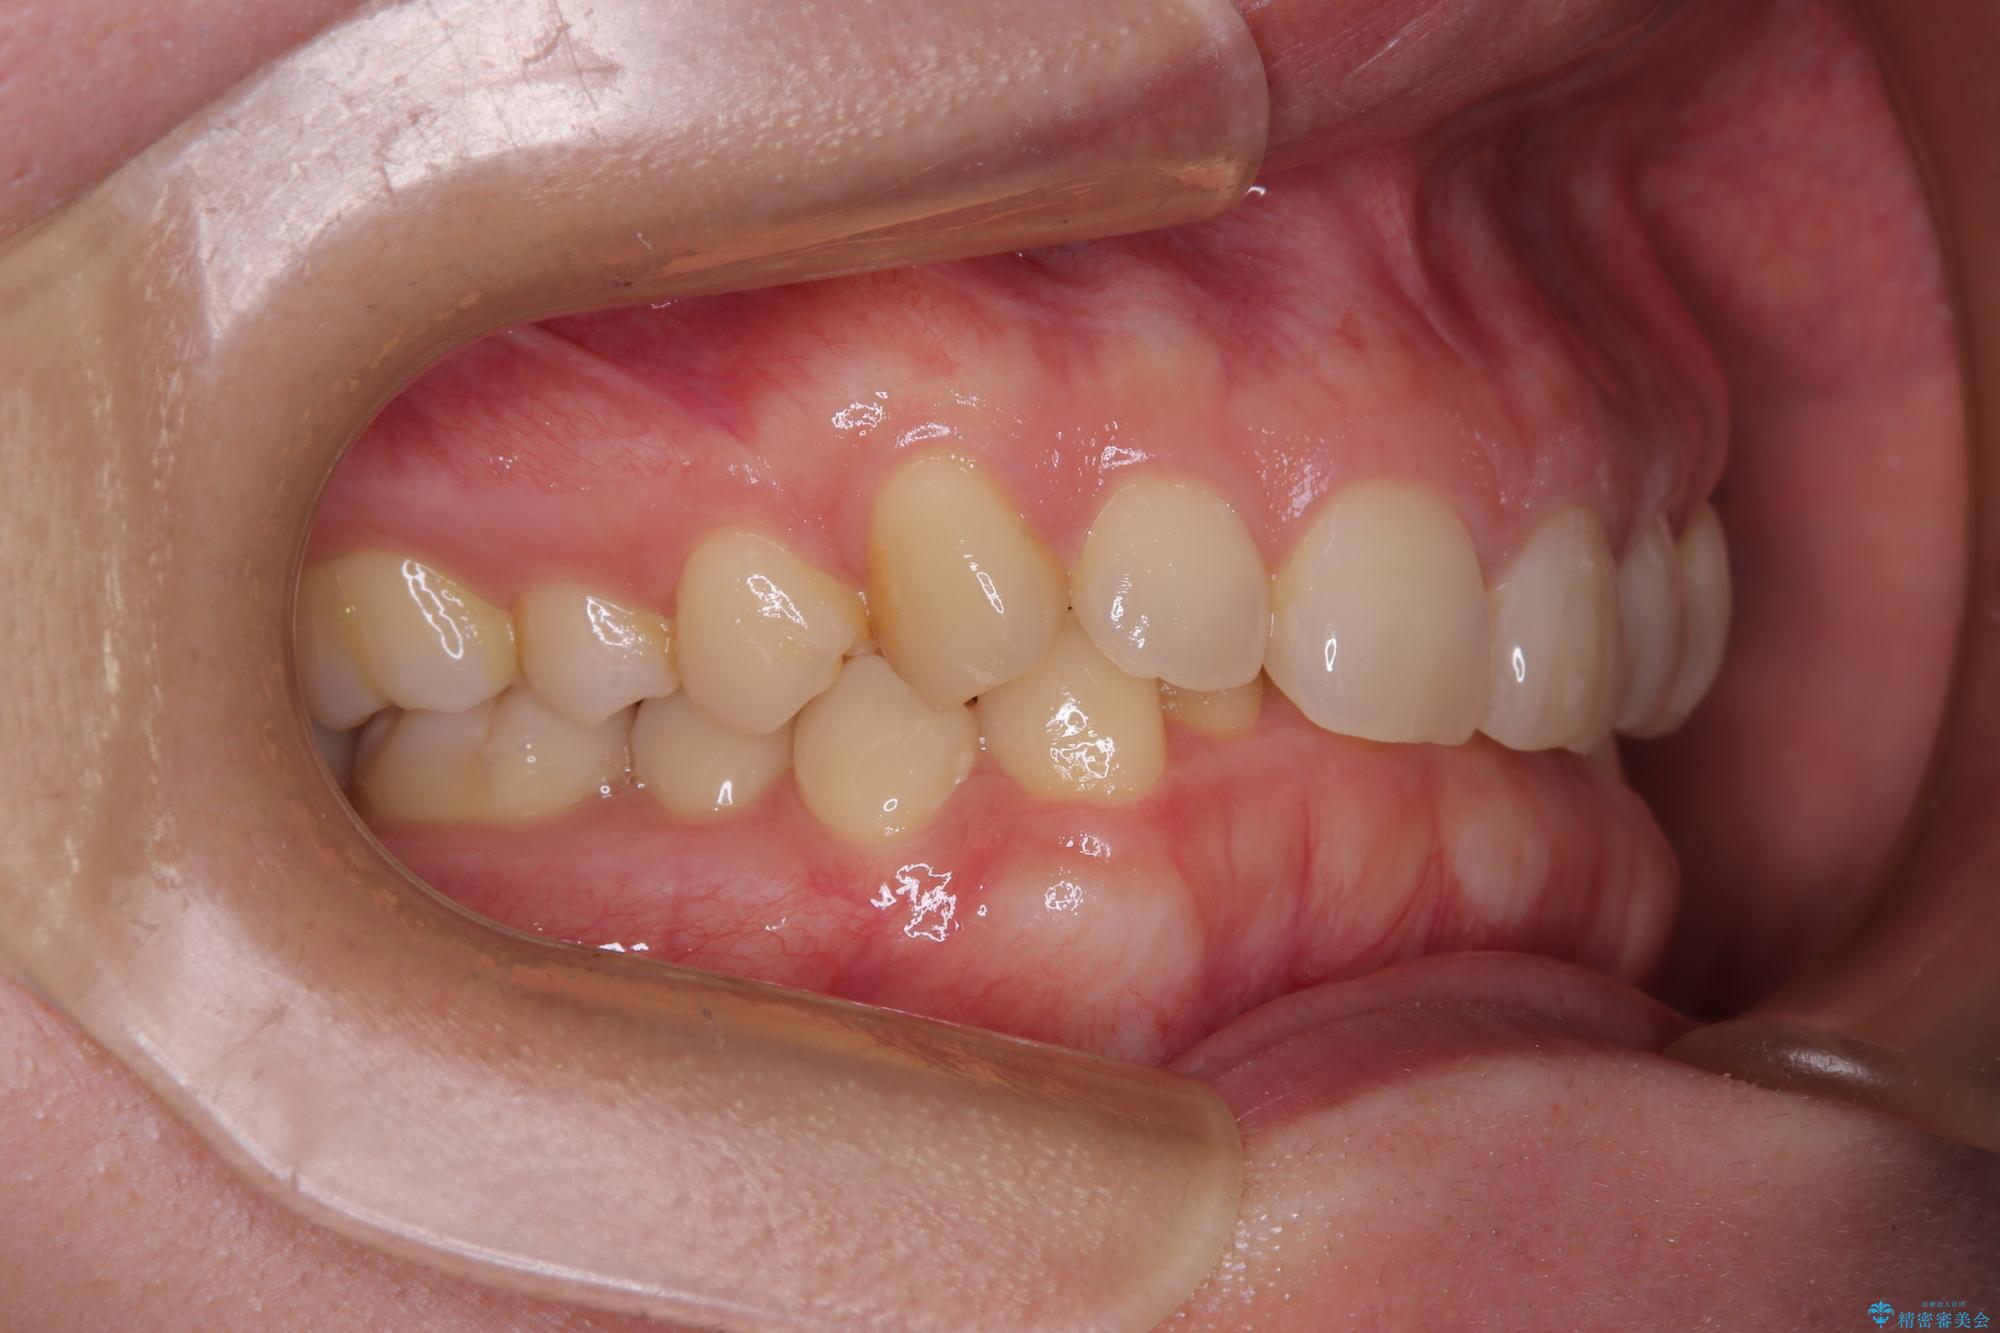

下顎の臼歯が手前に傾斜していることで咬み合わせが深くなってしまい、下顎前歯が見えないほどに上顎前歯が覆い被さっている状態でした。

咬合力が強いことと、マウスピースを長時間装着する自信がないとのことで、ワイヤー装置にて矯正治療を行うこととしました。